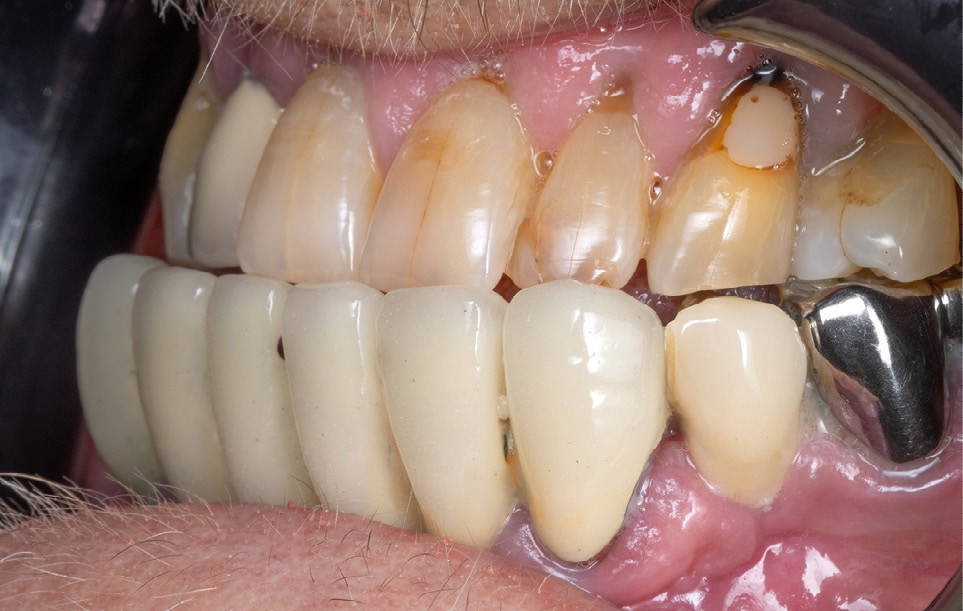

La première étape repose sur la récolte des données cliniques suivantes : – photographies exo- et endo-buccales (fig. 1), utilisées pour l’évaluation esthétique, le diagnostic initial et la communication avec le prothésiste ;